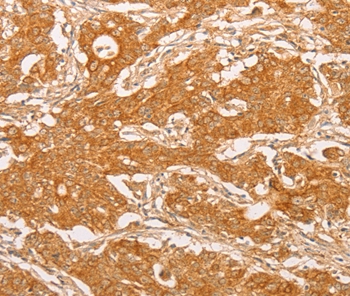

Immunohistochemical analysis of paraffin-embedded Human gastric cancer tissue using #36199.

Immunohistochemistry: 1:25-1:100